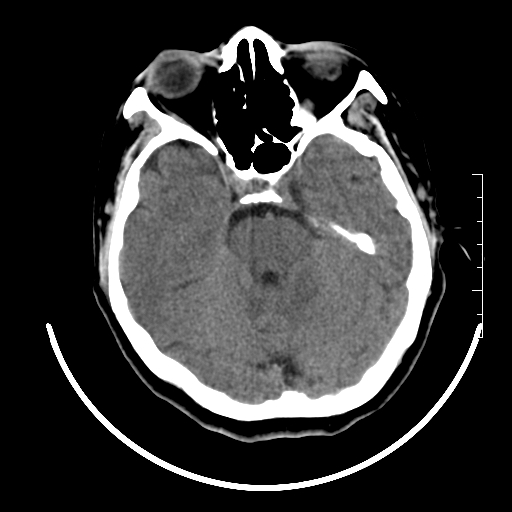

标题: CT27880:f、55y,头痛。 [打印本页]

标题: CT27880:f、55y,头痛。

考虑左侧顶部镰旁脑膜瘤;建议行ct增强扫描检查。

考虑左侧顶部镰旁脑膜瘤,建议行ct增强扫描检查。

考虑左侧顶部镰旁脑膜瘤;建议行ct增强扫描检查

大脑镰旁脑膜瘤可能,建议增强或mri

镰旁小脑膜瘤可能性大

左侧顶部镰旁脑膜瘤,增强